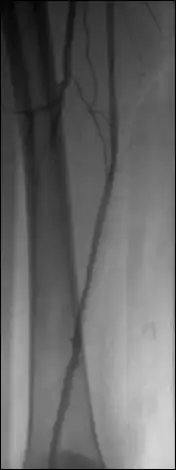

The image number used for the mask image is displayed – the first image of the sequence is the default mask. Browse through the sequence and adjust the WL/WW as needed. Click on the ‘current’ button to select another mask image.

Use the up/down arrows to shift the relative position of the mask and live images in single pixel increments in both horizontal (X) and vertical (Y) dimensions, if needed.

Note than finer shifts than whole pixels are a feature yet to be implemented in OsiriX.